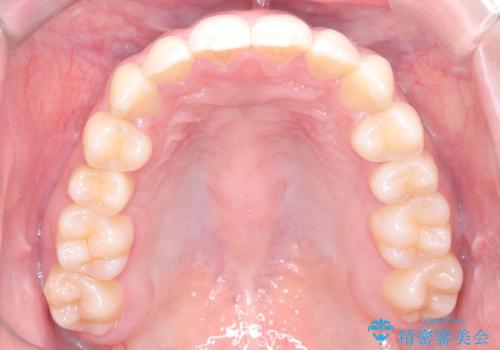

- 右上の小臼歯が大きくねじれており、噛み合わせや見た目に影響を与えている状態でした。診察の結果、インビザライン単独では十分な回転が得られにくいと判断。そのため、基本的な歯列の移動はインビザラインで行いながら、部分的にワイヤー矯正を併用するコンビネーション治療を計画しました。

まず、インビザラインで歯列全体を整えながら、スペースを確保しました。その後、部分ワイヤーを装着し、右上小臼歯の捻転を効率よく改善。ワイヤーの力を活用することで、より確実に歯の向きを整えることができました。治療後は、「しっかり噛めるようになり、見た目も自然になった」と患者様にもご満足いただきました。